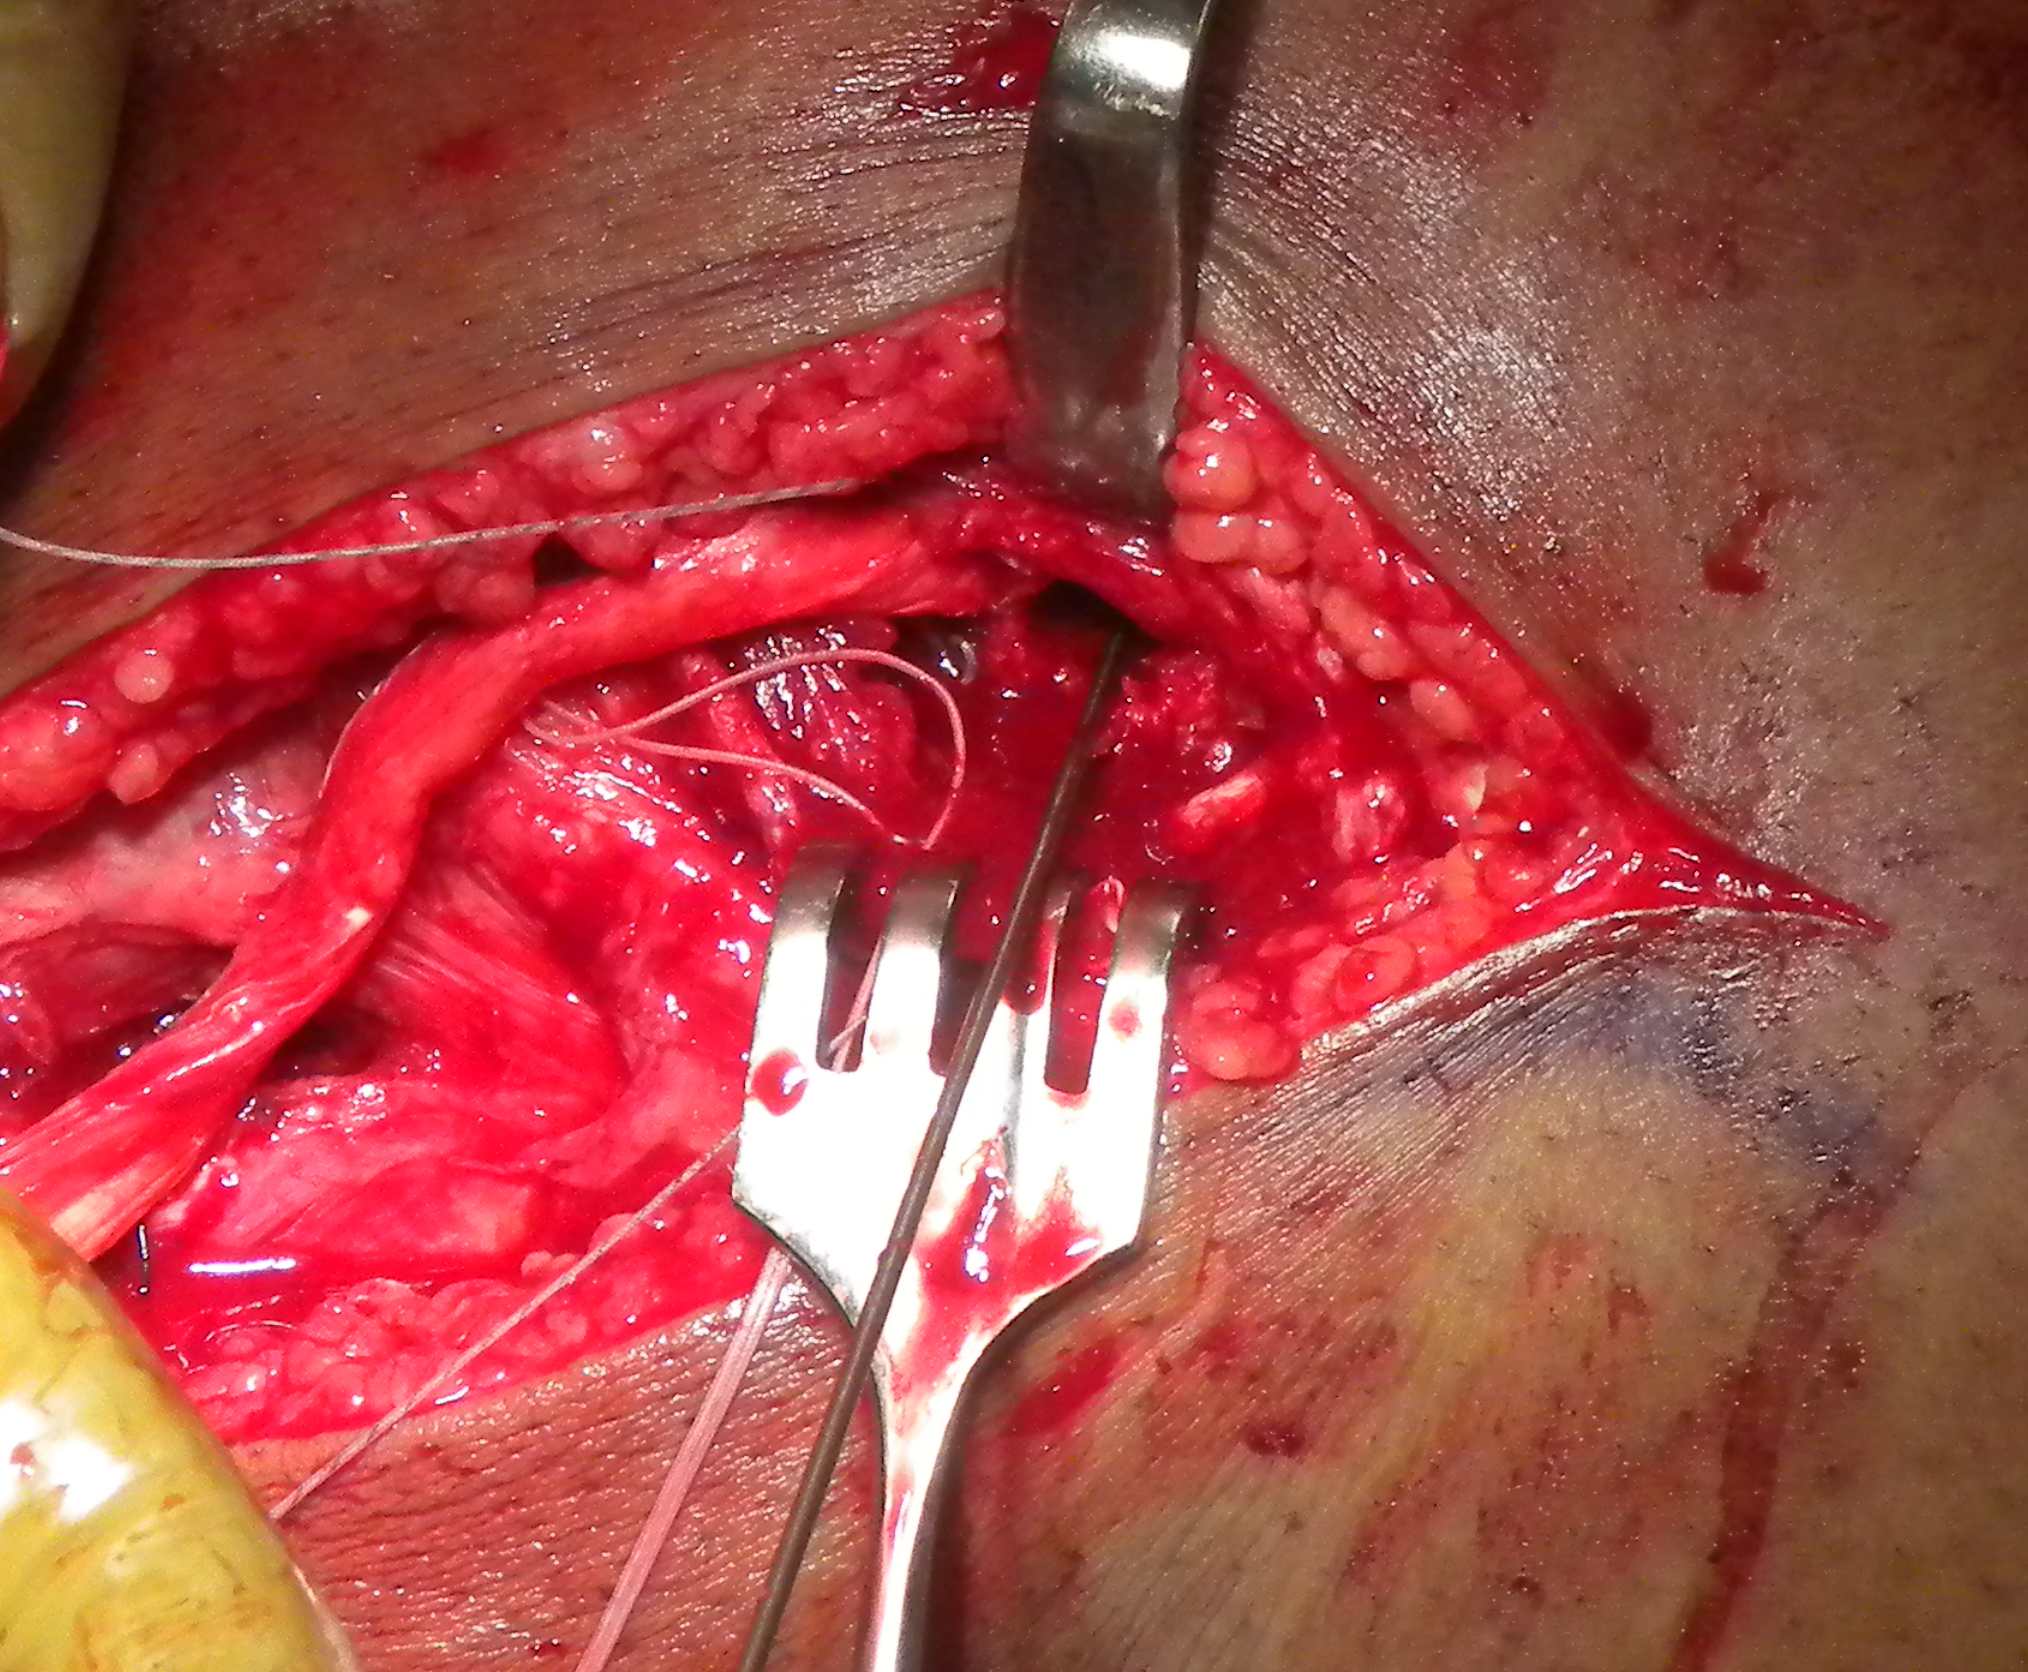

Surgical approach to posterolateral corner

PLC Dissection 1PLC Dissection 2

2.  Between biceps and ITB

Elevate posterior border to ITB

- identifies the fibular head

- LCL fibular insertion

- posterolateral window for exposing tibia

3.  Bisect ITB

Dissect onto epicondyle

- femoral insertion LCL

- femoral insertion popliteus

Identify femoral insertion of LCL and popliteus

Can tag LCL on fibular head

- pulling on it will identify femoral insertion

- insertion is 1.4 mm proximal  and 3 mm posterior to lateral epicondyle

Open popliteal sulcus

- follow popliteal tendon into insertion at anterior 1/5 of sulcus

- this is intra-articular

- distal and anterior to LCL insertion

- 18.5 mm from LCL insertion

PLC Popliteus and LCL Femoral Drill HolesPLC Allograft Femoral Screw

PLC Pass Popliteus Tendon deep to fascia

PLC LCL Allograft Deep to Fascia

PLC Popliteus Allograft Anterior Through Tibia